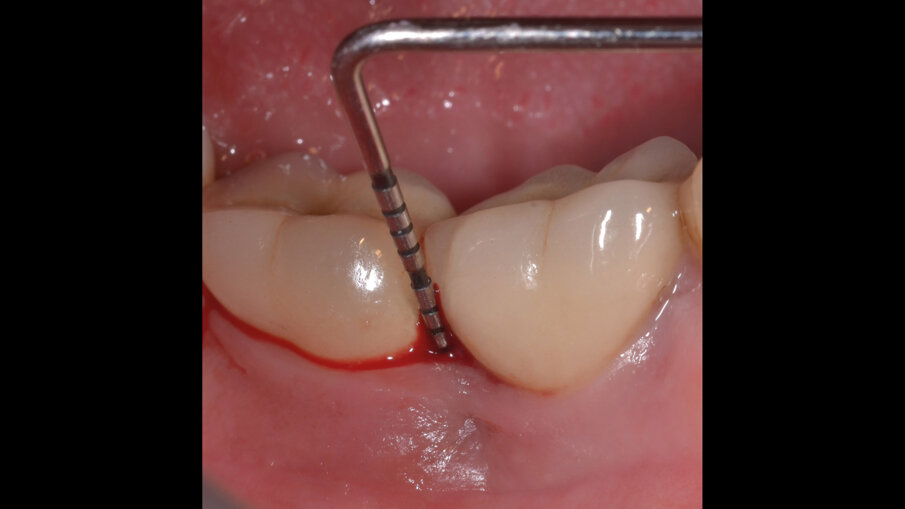

Il paziente, di sesso maschile e di 48 anni di età, è in buone condizioni di salute generale ma, a distanza di 10 anni dall’inserimento, presenta due impianti endossei, in posizione 4.6 e 4.7 con uniforme perdita ossea e con sondaggi di profondità variabile tra 6 e 9 mm accompagnati da sanguinamento, con tessuti marginali che mostrano importanti aspetti infiammatori, causa di sintomatologia dolorosa per il paziente (Figg. 1a-f).

I siti interessati sono stati strumentati per via non chirurgica, utilizzando strumenti manuali, strumenti ultrasonici e air polishing con eritritolo. Al termine della seduta è stato applicato il gel di ozono (Ozosan Gel - Bioactiva) all’interno delle tasche, lasciando agire il dispositivo per 8 minuti, quindi eseguendo lavaggio con soluzione fisiologica. Il post-operatorio ha avuto un decorso privo di dolore con rapida remissione della sintomatologia soggettiva. Il paziente è stato inserito in un programma di mantenimento parodontale trimestrale. A distanza di 6 mesi dal trattamento non chirurgico della perimplantite, i siti si presentano stabili con profondità di sondaggio ridotta tra i 3 e i 5 mm con assenza completa di sanguinamento al sondaggio (Figg. 1g-m).